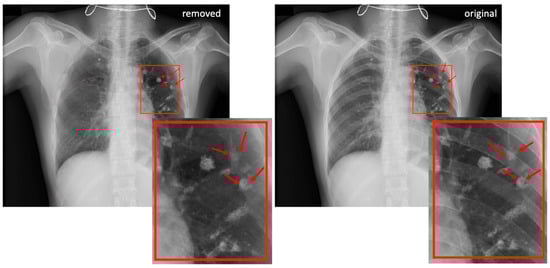

3.2.1. NOD21 Detection